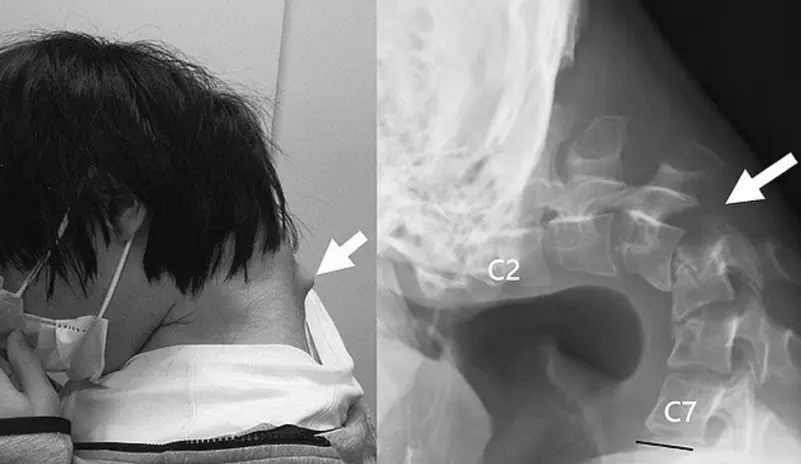

وتظهر الصور المروعة انتفاخا بارزا من رقبته، والذي عزاه المسعفون إلى "تمدد فقراته بشكل كبير" عن الوضع غير الطبيعي، بحسب ما نقلت "ديلي ميل".

وكشفت صور الأشعة التي أجراها أطباؤه أن فقرات رقبته قد تشوهت وانخلعت، مما أدى إلى نمو أنسجة تشبه الندبات في العمود الفقري بمرور الوقت.